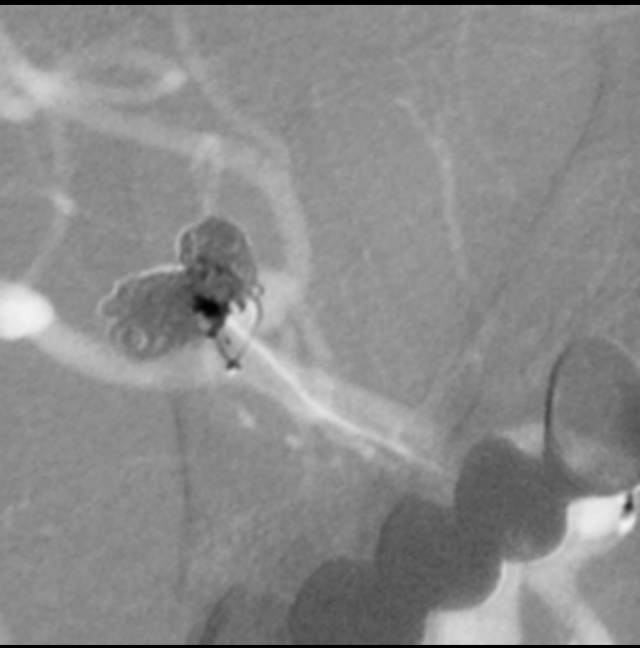

我们在工作中,有时也会遇到比较棘手的问题。譬如下面这个破裂的分叶状的宽颈动脉瘤,两个不大不小不能忽视的子囊还拥有一个共同的大本营—绝对宽颈的瘤体,动脉瘤也通过“犄角之势”成为一个硬骨头,想要拿下它绝非易事。单独出兵(栓塞)容易孤兵深入,首尾难顾,甚至可能需要采用挽救性技术来搬救兵保护粮道(载瘤动脉),万一失利,劳师伤财;使用1-2个支架辅助手术呢,由于急性期抗血小板不足术中可能出现急性血栓堵塞粮道,万一瘤体又不能致密栓塞一网打尽,术后抗血小板吧,怕出血;不抗血小板吧,又担心血栓。一旦遭遇此种境遇,战争(手术)的走向和主动权就无法掌握在指挥者(术者)手中,只能听天由命了……

话归正传,下面我们看看如何分兵使用“犄角之势”的策略夹击栓塞“犄角之势”的硬骨头(分叉部绝对宽颈带有俩角的动脉瘤):两个微导管先后到位,两个子囊内的弹簧圈相互依偎,形成“犄角之势”,共同击杀两者之间的大本营(共同的瘤体),最终致密栓塞动脉瘤,消除了动脉瘤再次兴风作浪(再出血)的风险,也最大限度的保全了各个分支血管(粮道)的安全,急性期也没有使用支架,降低了费用,还保障了安全。